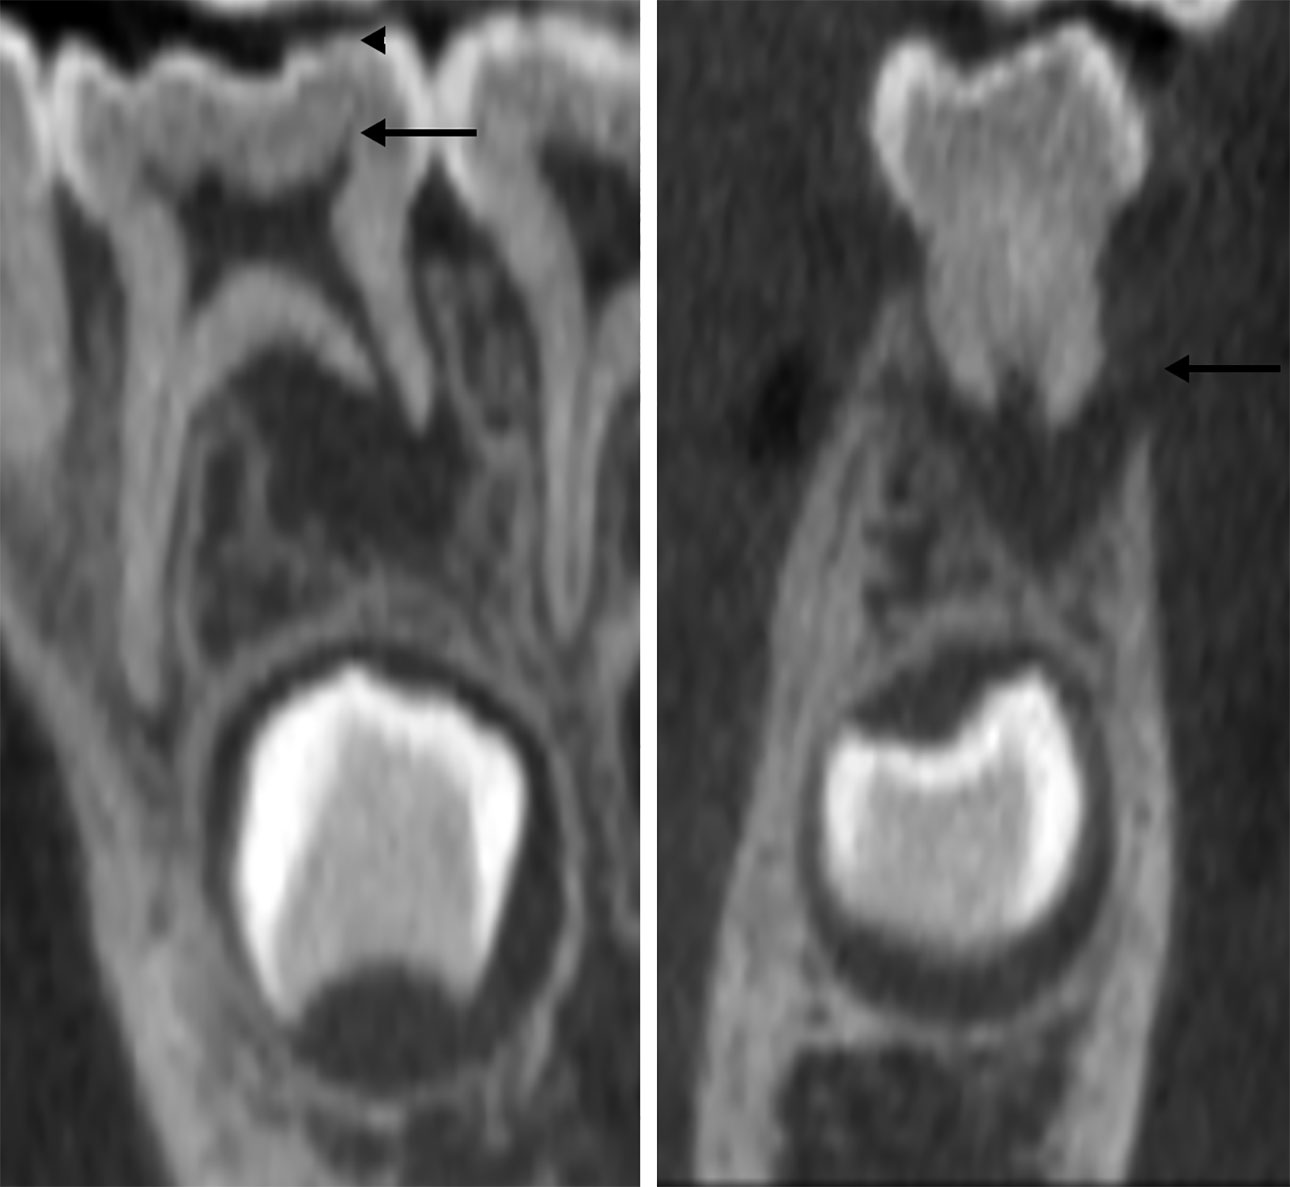

Pasienten ble henvist til Avdeling for kjeve- og ansiktsradiologi for videre utredning av omfanget og mulig årsak til osteolysen, inkludert mulighet for annen diagnose. Småfelts CBCT-undersøkelse (J. Morita Corp. Accuitomo XYZ) ble utført med raskest mulig skannetid for å redusere risikoen for bevegelsesartefakter og gi lav stråledose tilpasset aldersgruppen. Undersøkelsen bekreftet periapikal osteolyse ved den distale roten, opp til rotfurkasjonen, og viste i tillegg totalt manglende ben bukkalt for roten. Som ved klinisk og periapikal røntgenundersøkelse kunne det ikke påvises emaljedefekter i kronen, men et stort distalt pulpahorn ble mistenkt (figur 2).

Figur 2. Henholdsvis skrått sagittalt (venstre) og skrått koronalt (høyre) bildeutsnitt fra CBCT-undersøkelsen viser periapikal osteolyse ved distale rot tann 74 og osteolyse av tilstøtende bukkal korteks (pil høyre bilde). Det skrå sagittale bildeutsnittet gir inntrykk av et langt distalt pulpahorn (pil venstre bilde), men intakt okklusal emalje (pilhode venstre bilde).